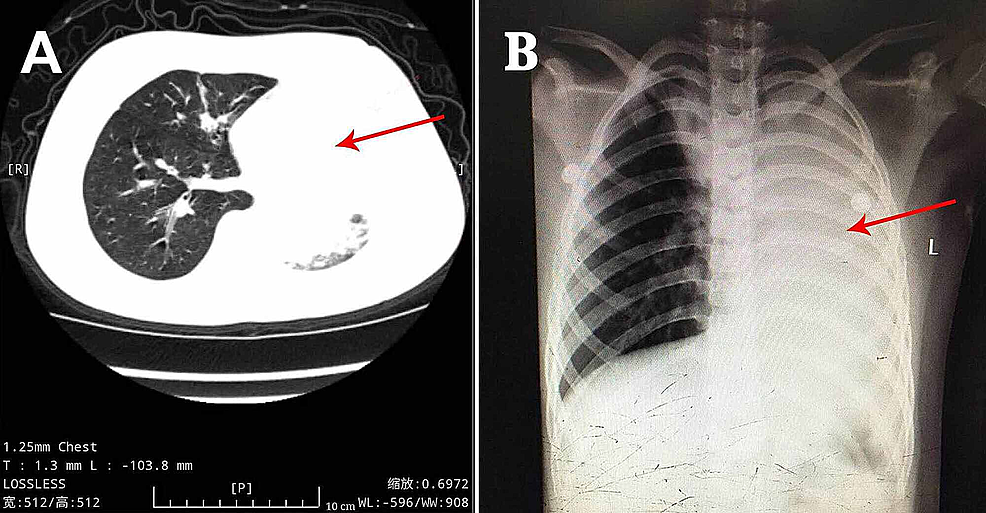

A previously healthy eight-year-old boy, without the history of wheezing and foreign body inhalation, was transferred to the emergency center of Jiangxi Provincial Children's Hospital from a basic-level hospital with a two-day history of fever, cough, and progressive dyspnea. His body temperature was approximately 38 °C. He had been previously treated with antibiotics at a local hospital without improvement except the normalized body temperature. Subsequently, he underwent chest computed tomography (CT) scans, which revealed atelectasis in the left lung and a foreign body in the left upper bronchus, along with pneumonia in the right lung (Figure 1A). In our emergency department, physical examination showed clouding of consciousness, cyanosis, rales, and diminished breath sounds in both lungs. Other parameters were as follows: body temperature, 36.9 °C; heart rate, 150 beats/minute; respiratory rate, 46 breaths/minutes; percutaneous oxygen saturation, approximately 70% under high-flow oxygen therapy. Since the local chest CT scan and clinical manifestations indicated a high possibility of foreign body inhalation, urgent bronchoscopy was performed. This procedure did not reveal the presence of any foreign body in the trachea of this patient but showed the presence of white gelatinous secretions that completely blocked the left main bronchus. Upon removal, it was observed that the secretions are shaped like a bronchial tree (Figure 2A). However, after this cast removal followed by bronchial lavage, there was no significant improvement in oxygen saturation, which fluctuated between 70% and 80%. The patient was admitted to the pediatric intensive care unit and intubated immediately.

After the observation of the cast that was removed via bronchoscopy, PB diagnosis was confirmed. Further, histopathology indicated that the casts predominantly comprised of inflammatory necrotic tissue, mucin, numerous neutrophils, and eosinophils (Figure 2C). Chest X-ray revealed pneumonia in both lung lobes and atelectasis in the left lung (Figure 1B), suggesting airway blockage by residual casts. Furthermore, complete blood count revealed the following: white blood cells, 13.11×109 cells/L (leukocytosis); neutrophils, 85.4%; hemoglobin, 145 g/L; and platelets, 350×1012/L. The blood biochemistry results of this patient were as follows: C-reactive protein (CRP), 42.6 mg/L; IgE, 908.4 IU/ml; IgA, 1.04 IU/ml; IgM, 0.62 IU/ml; and IgG, 12.15 IU/ml. As PB diagnosis is confirmed, along with extensive inflammatory necrotic tissue in the casts, we started treatments as follows: imipenem-cilastatin sodium (30 mg/kg, q6h) for anti-infection; azithromycin (10 mg/kg, qd); intravenous methylprednisolone (1 mg/kg, q12h); nebulized dexamethasone (5 mg, q6h) for anti-inflammation; nebulized bronchodilators, intensive chest physiotherapy, and intravenous mucosolvan for mucolytic therapy. However, oxygen saturation still fluctuated at approximately 80% without improvement for the next two days. Sputum etiology examination was positive for influenza A virus and negative for other viruses and Mycoplasma pneumoniae RNA, as well as fungi and bacteria. Additionally, blood cultures for bacteria and fungi were also negative.